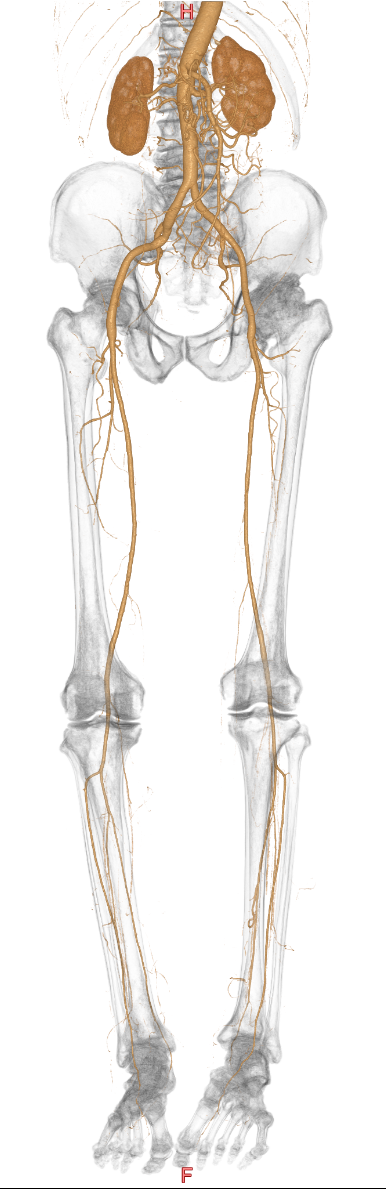

【下肢動脈CT】

足を栄養する血管である下肢動脈の走行や詰まっているところ、狭くなっているところがないかを調べる検査です。

主に下肢閉塞性動脈硬化症の診断や治療方針を決めるのに有用です。

寝台に仰向けで寝た状態で足を固定して造影剤を注入して撮影をします。